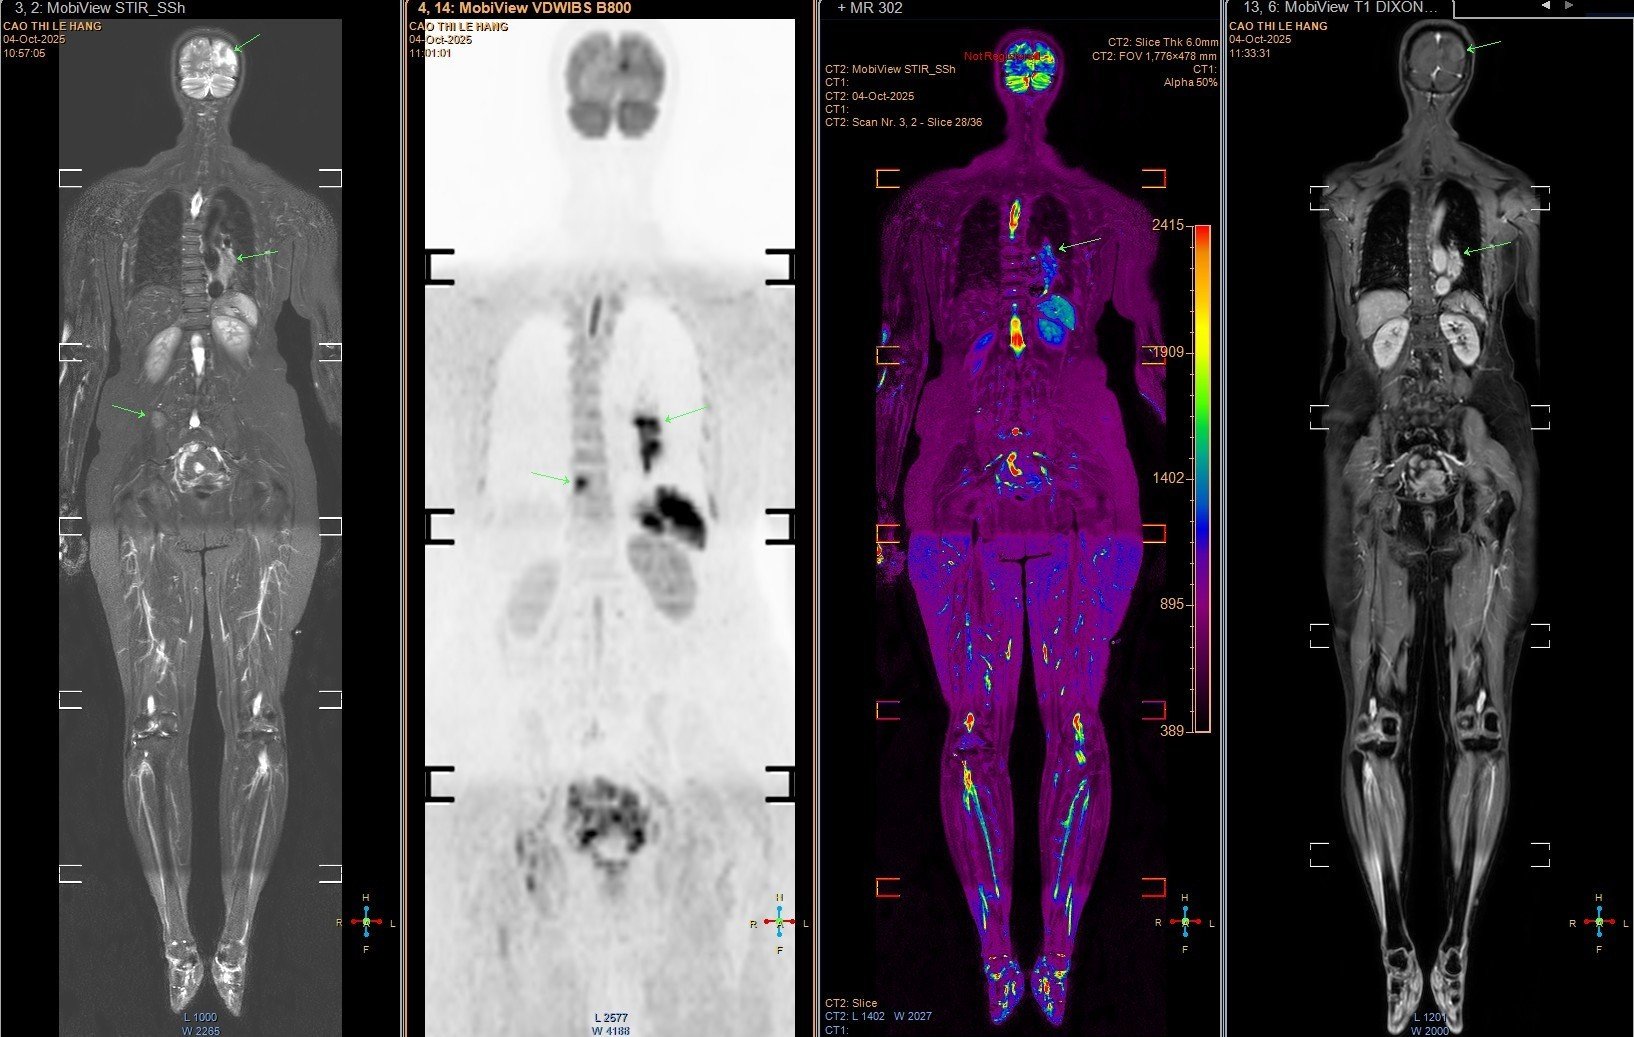

Người phụ nữ 63 tuổi phải nhập viện vì những cơn đau đầu, chóng mặt kéo dài mà ban đầu bà tưởng là rối loạn tiền đình. Qua thăm khám chuyên sâu, các bác sĩ phát hiện ra một sự thật đau lòng: bà bị ung thư phổi giai đoạn cuối, khối u lớn ở đáy phổi trái đã di căn lên não, cột sống và xương chậu, tiên lượng rất xấu.

- Các kỹ thuật hiện đại như PET/CT, PET/MRI kết hợp sinh học phân tử giúp xác định đột biến gen và lựa chọn phương pháp điều trị trúng đích hiệu quả.